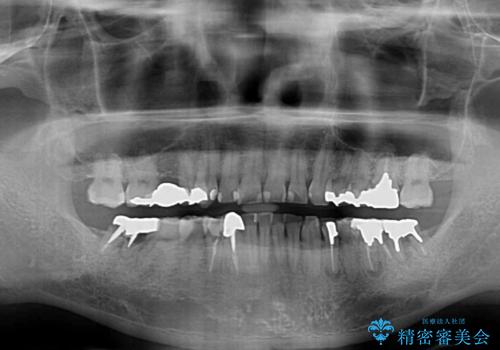

- 近医にて下顎奥歯の抜歯が必要と言われたとのことで来院された患者様です。

診察の結果、奥歯は左右ともに抜歯が必要な状態でした。

他の銀歯も気になっており、セラミックにしたいとの要望があり、詳しくお話をすると、デコボコの歯ならびも整えたいとのことでした。

抜歯が必要な歯は事前に抜歯をし、その後ワイヤー装置にて歯列矯正を行い、途中でインプラントを埋入し、オールセラミッククラウンにて補綴治療を行うこととしました。